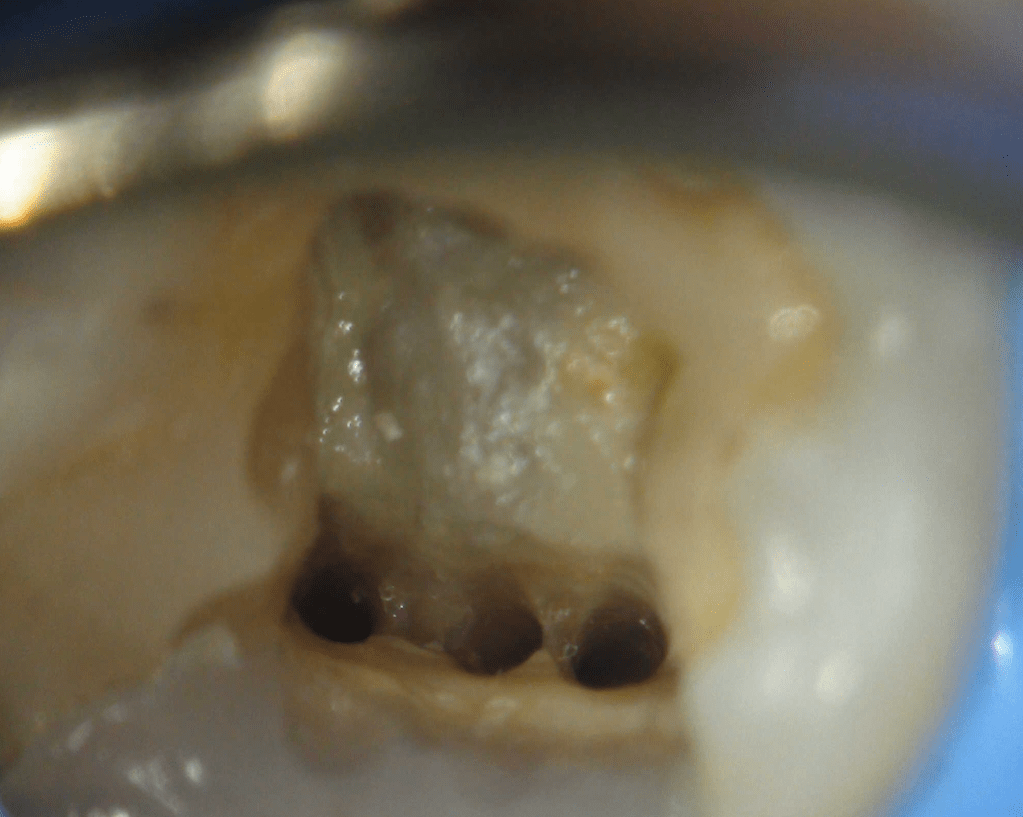

Reconstrucción preendodóntica

Reco pared vesticular

Reco pre-endo, molar inferior

Reco preendo + 4 conductos molar superior

Reco preendo, 2o Molar superior